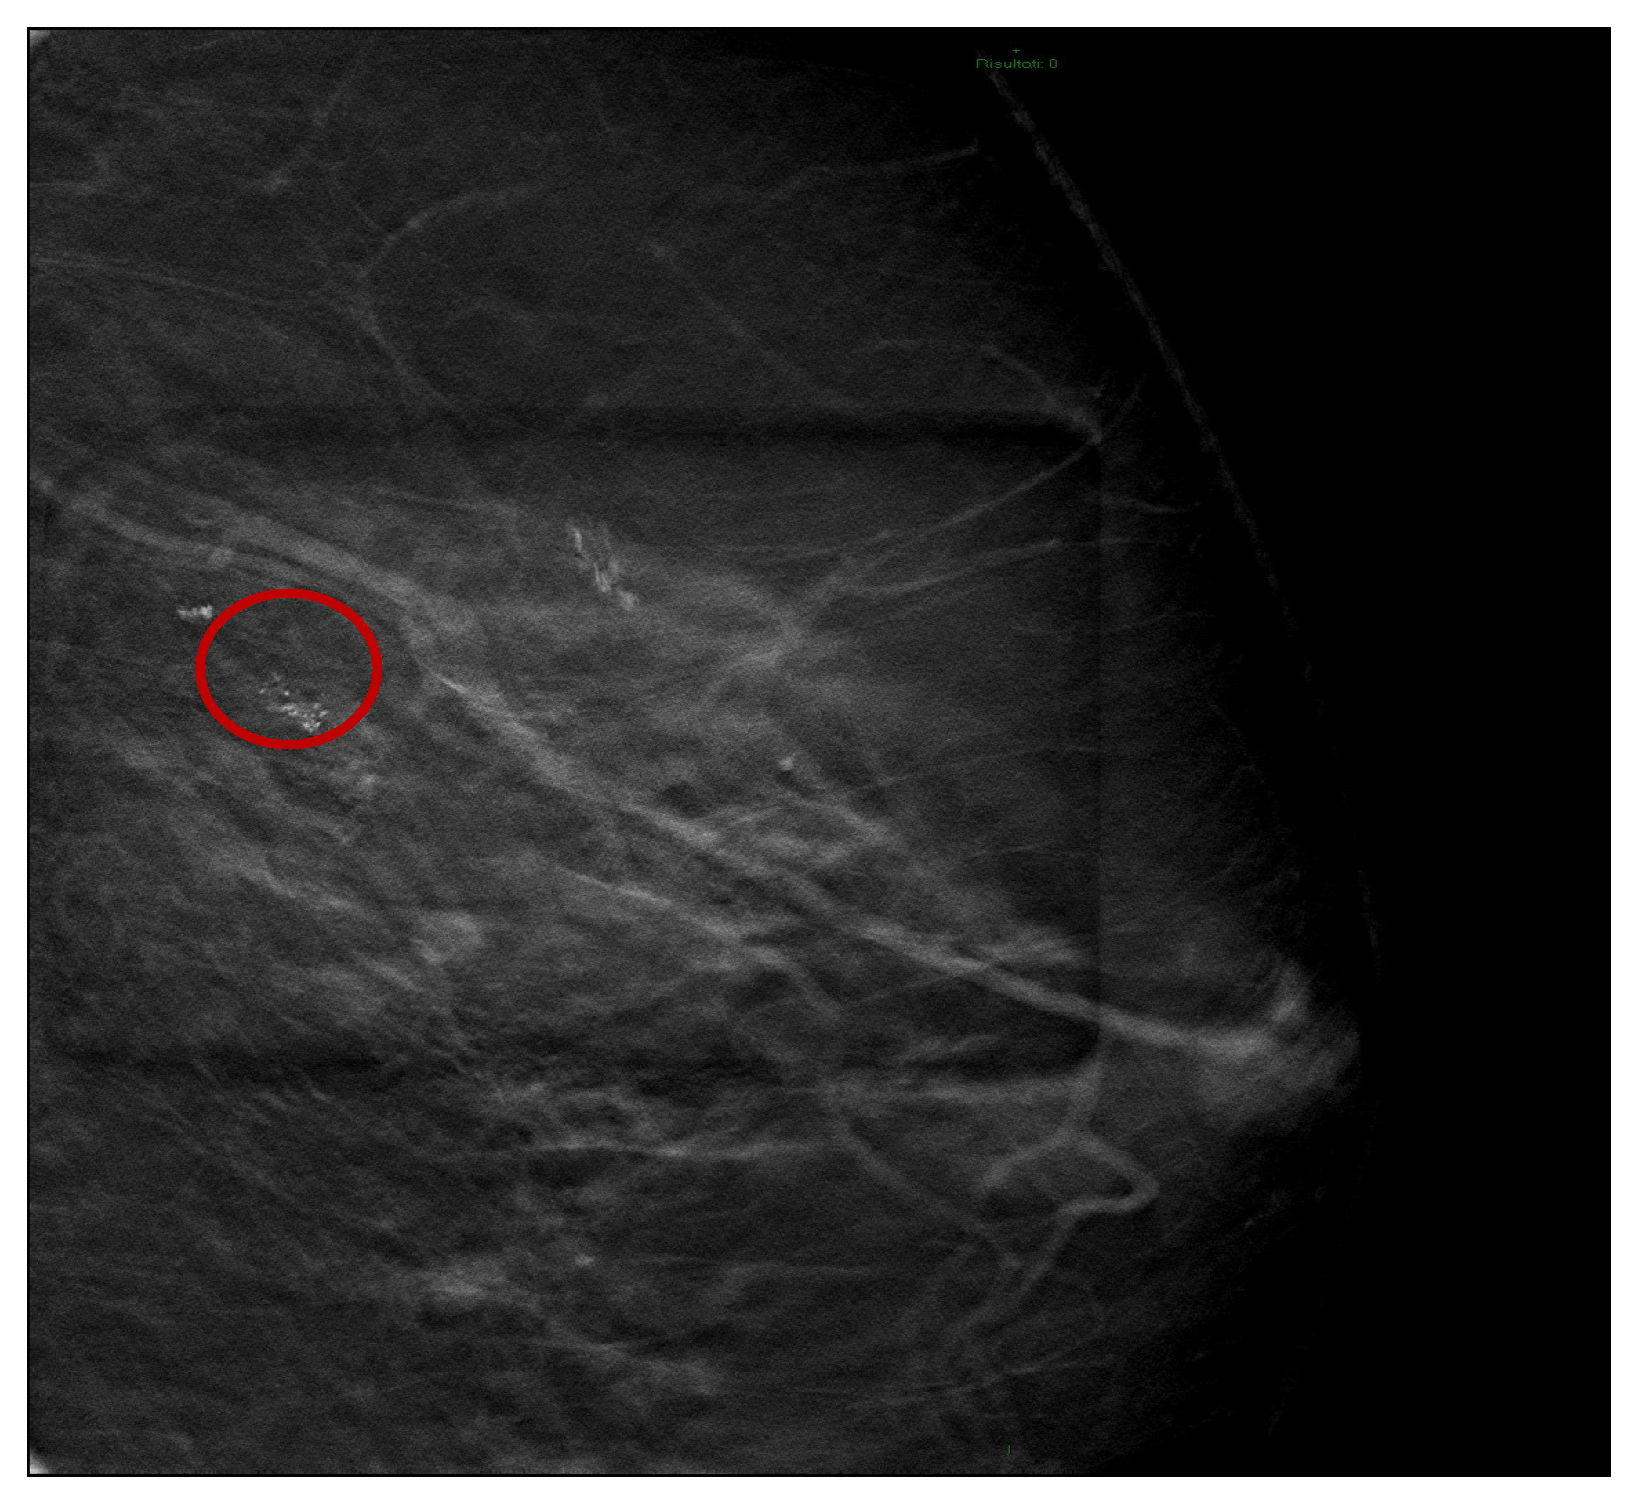

Vascular Complications following Vacuum-Assisted Breast Biopsy (VABB): A Case Report and Review of the Literature

2. Case Report